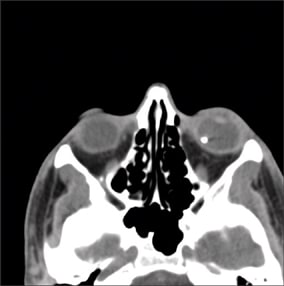

A 20-year-old male sustained an intraocular foreign body (IOFB) in his left eye by hitting a hammer against a large metallic object. He presented to the emergency room 1 day after the injury. On examination, his visual acuity was 20/200, and a large nasal conjunctival hemorrhage was observed with hypotony and clear cornea and lens. On indirect funduscopy, a metallic intraocular foreign body was observed stuck in the inferior retina at the equator with a local retinal detachment, whitening of the retina around its edges, and a mild vitreous hemorrhage. The intraocular foreign body was demonstrated on orbital CT (Figure 1). An exploration revealed a 4 mm entry wound, extending posteriorly from the limbus at the nasal side. The wound was sutured with Vicryl 7/0 suture, an encircling #41 solid silicone band was placed (Figure 2), and a pars plana vitrectomy was performed during the primary procedure. The intraocular foreign body was released from its adhesions to the retina (Figure 3) and removed with a magnet (Figure 4) through a previously prepared sclerotomy, revealing a large retinal tear (Figure 5). The intraocular foreign body outside the eye is shown in Figure 6.

Figure 1. Preoperative axial CT with metal intraocular foreign body.

■ Imaging. Computed tomography (CT) of the orbits without contrast is the test of choice in suspected globe perforation. Thin axial-section CT scan should be performed to evaluate the orbital and facial bones, retrobulbar space, and globes. Particular attention should be given in cases of shrapnel injuries or when multiple facial lacerations are observed. When an IOFB is found on CT scan, its size, shape, location, and composition if possible (eg, metallic, wood, stone, vegetable matter) should be determined. A comparison between helical CT and conventional CT6 found the first to be superior in the preoperative assessment of patients with intraocular foreign bodies. It was associated with a shorter acquisition time with reduced motion artifact, decreased radiation exposure, and the ability to obtain reconstructed sagittal and coronal views for localization of an IOFB. It is also more sensitive than conventional axial CT, MRI, and ultrasound for the detection of glass IOFBs.7 B-scan ultrasonography may have a role in the management of IOFBs, but prior globe closure is required, given the risk of extrusion of intraocular contents.8